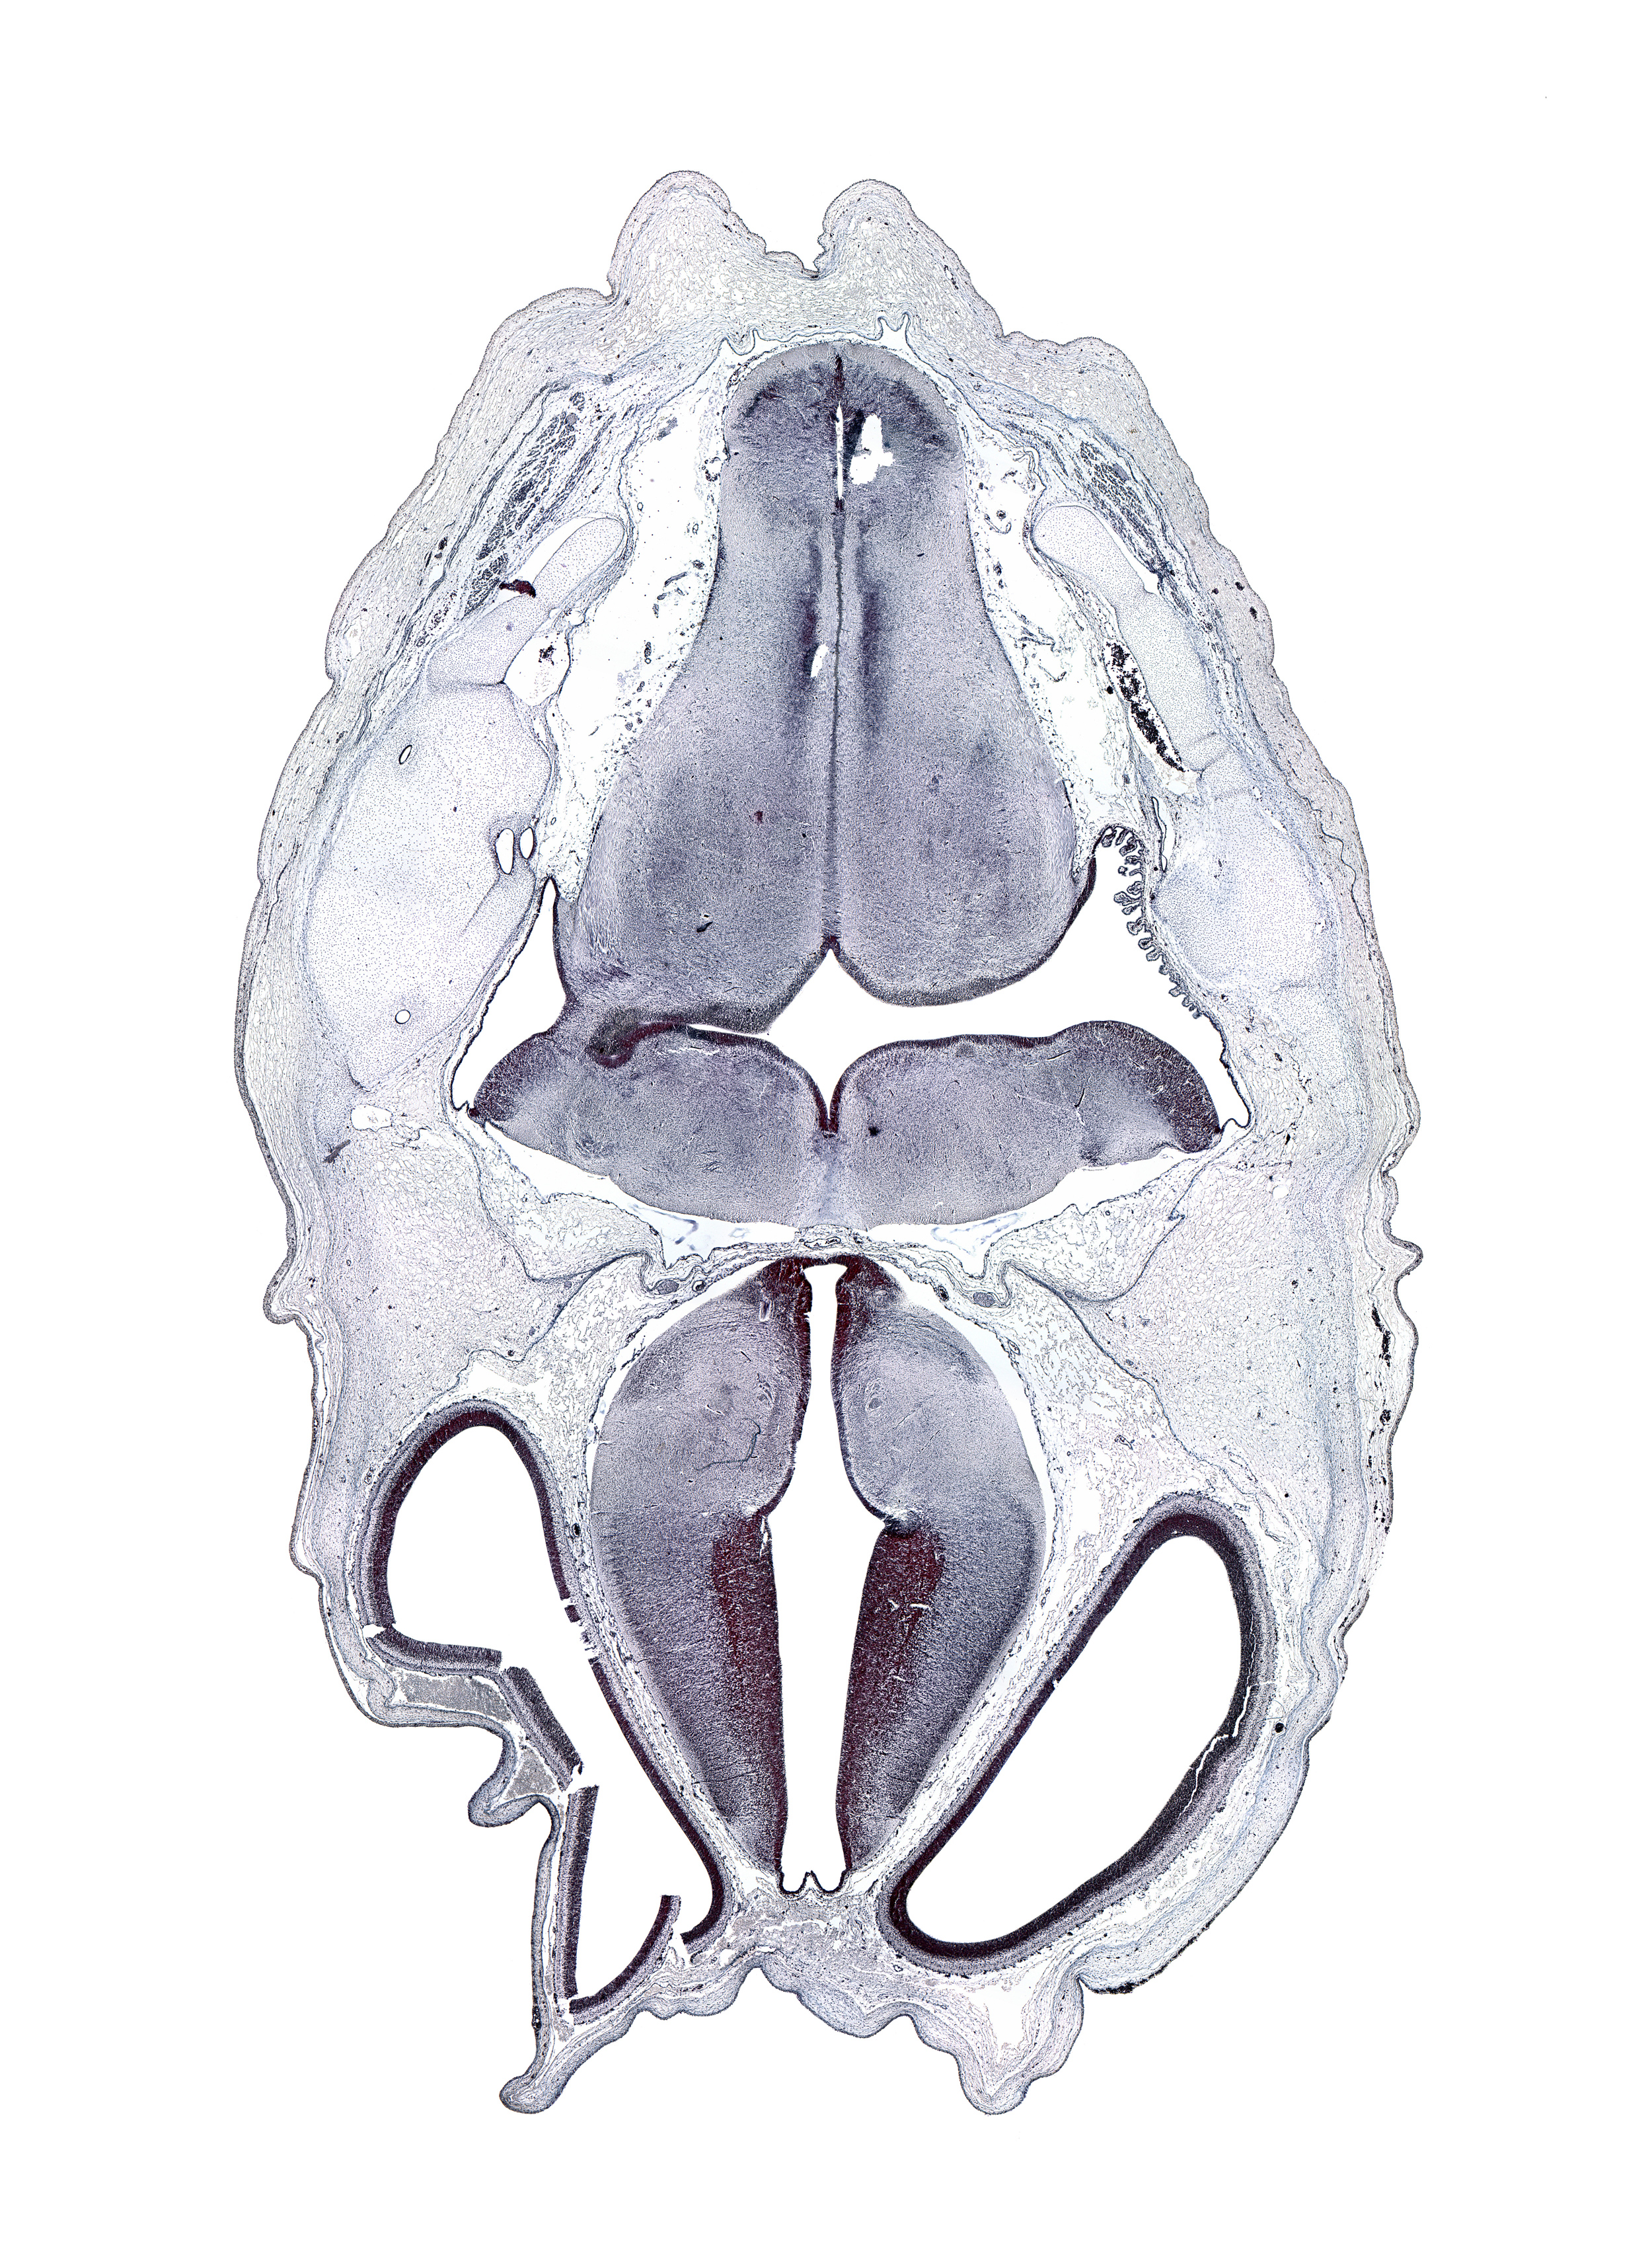

Boyd Embryo #H983 | Location: 42-1-1

Keywords: artifact space(s), artifact(s), decussation, hypothalamic sulcus, medial accessory olivary nucleus, medial longitudinal fasciculus, nucleus cuneatus, nucleus gracilis, oculomotor nerve (CN III), otic capsule cartilage, roof plate of diencephalon, sulcus dorsalis, sulcus limitans, transverse dural sinus, transverse sulcus in floor of rhombencoel (fourth ventricle)

Source: The Virtual Human Embryo.